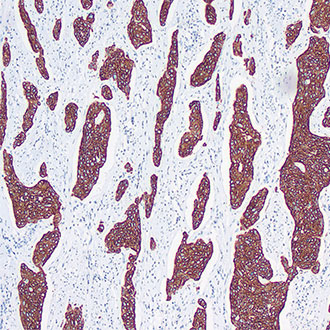

CK Pan

CK Pan -